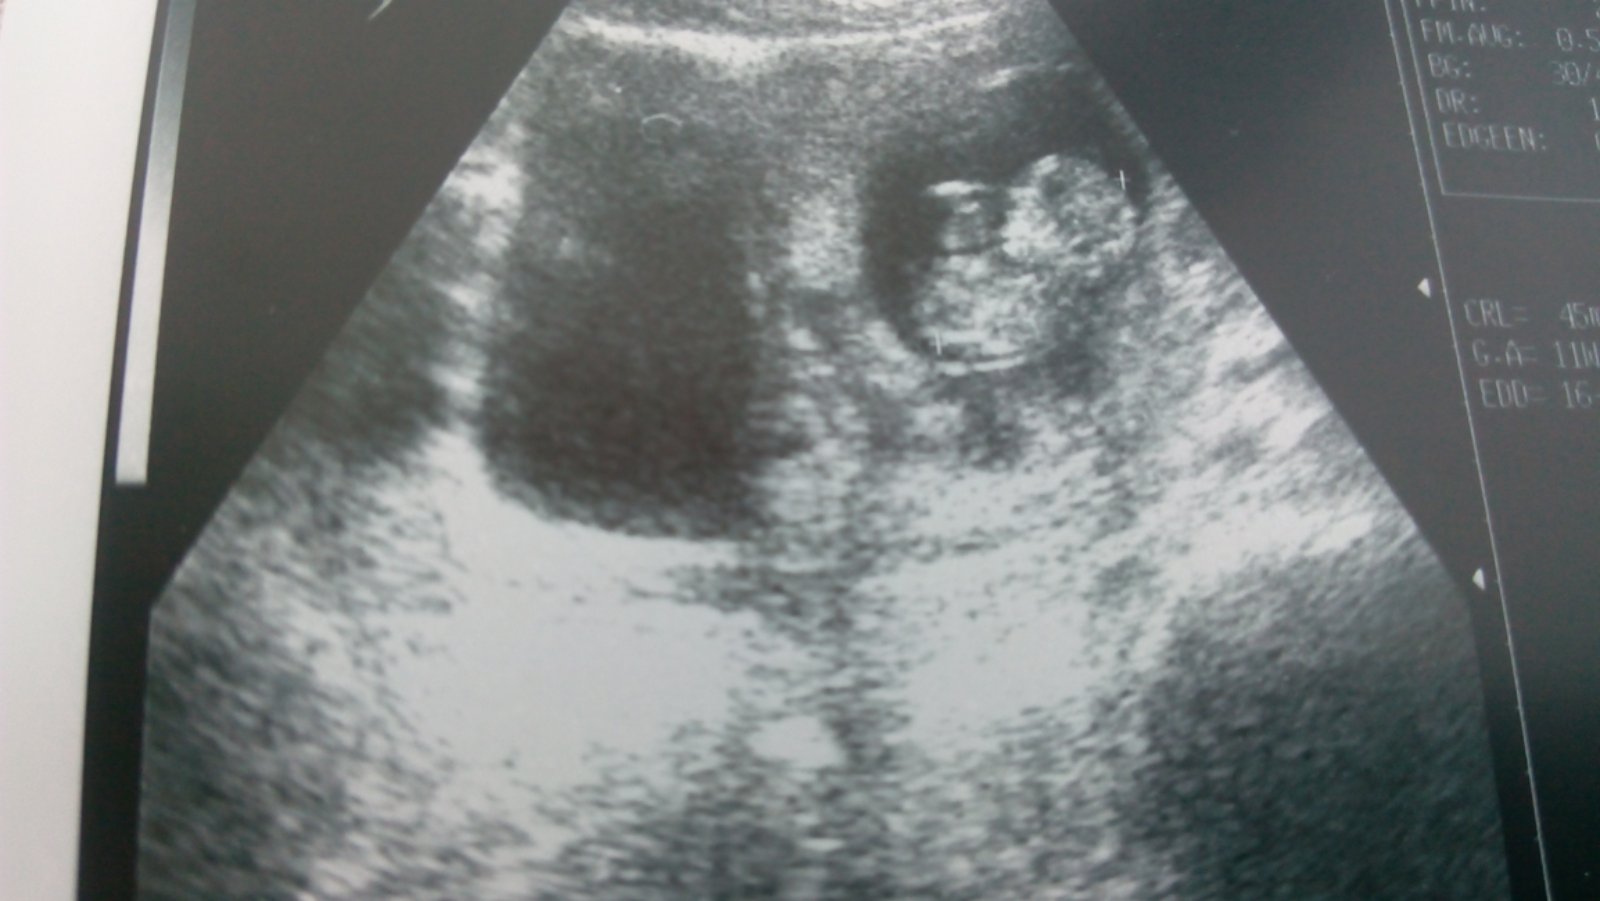

Toto je naša malá piškotka

@renata1981 no podla ma to bola fakt len viroza, nastastie mi uz nie je zle klop,klop,klop, teda rano mam taky zaludok na vode, ale to si dam citronovu vodu nalacno, to neutralizuje kyselinu, co ja mavam najviac, tak nechcem zakriknut ale pohoda klop,klop,klop. Buduci tyzden by som uz chcela ist konecne doktorke, som mala maleho dva tyzdne doma s tym uskom a som sa este ani nedostala.

Male zlate ako si tam lezka 🙂, tak super ze vsetko v poriadku, uz ti robili aj tie tripple testy? To sa takto nejako tusim robi ak si dobre pamata, ze 🙂?